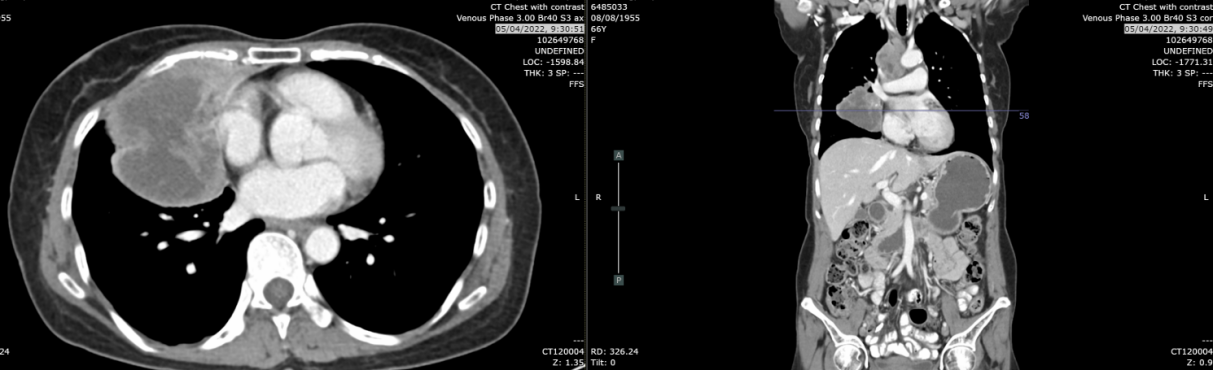

复查CT(2023-12-19):CT示肿块轻度增大至4.1cm(较7月增长24%),右肺上、中、下叶新见牵拉性支气管扩张及实变影,鉴别诊断包括浸润性转移、感染或混合性肺不张/实变。无肝、肾上腺、淋巴结或骨转移。

2024年3月21日:肿块缩小至2.8cm,实变及结节较前减少,考虑肺转移灶部分消退。

2024年6月17日:肿块略增至2.9cm,亚厘米级淋巴结。

2025年8月26日:肿块2.2cm,右肺上叶、中叶结节0.3-0.4cm稳定,中叶新增磨玻璃影(考虑感染或炎症),无新增转移灶。

疗效总结:自治疗开始计算,无进展生存期(PFS)达186周(3.5年);自停药后计算,PFS为102周(2年)。